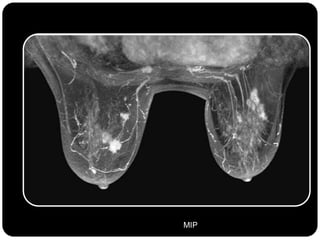

Paciente femenina de 66 años con historia clínica de 1er gesta antes de los 30 años y antecedentes de lactancia positiva, presenta una lesión palpable en la mama derecha. Los estudios radiológicos indican un diagnóstico de bi-rads 5, con biopsias revelando adenocarcinoma lobulillar infiltrante en la glándula mamaria derecha y adenocarcinoma ductal in situ en la izquierda. El caso fue evaluado por las doctoras Jacqueline Preciado Vargas y Beatriz E. González Ulloa.